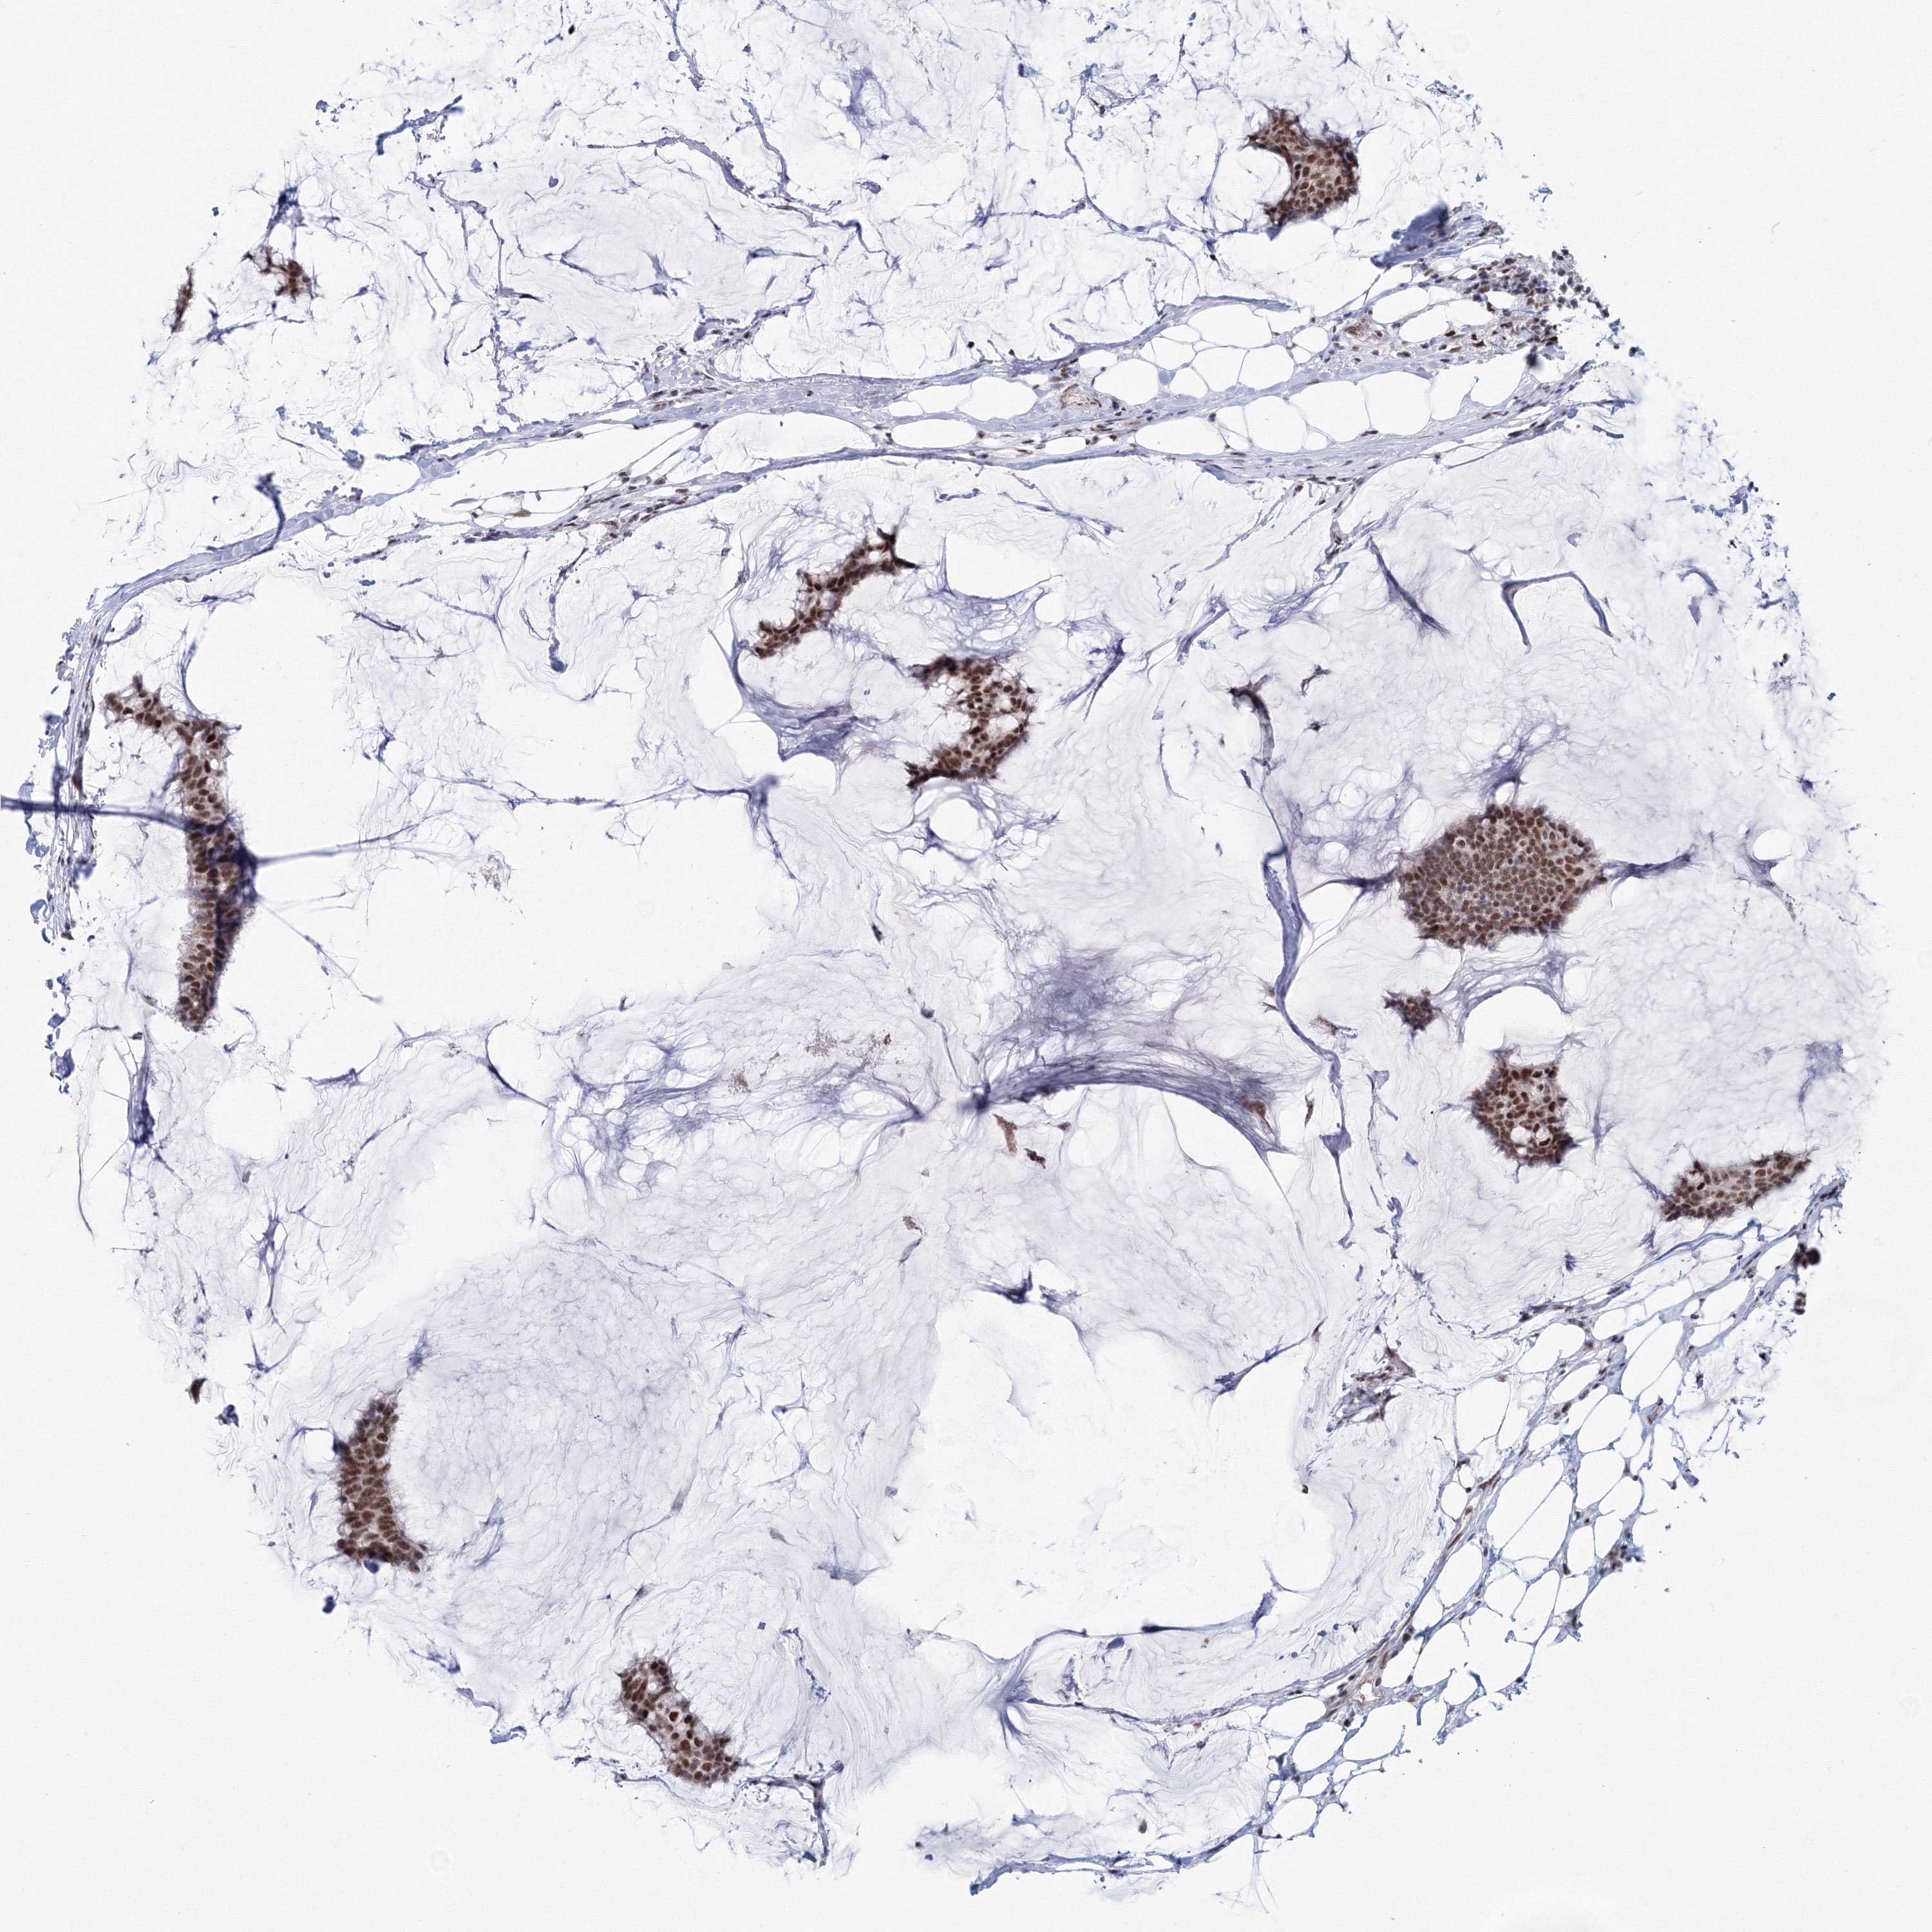

CANCER BREAST CANCER Show tissue menu

BRCA TCGA BRCA VALIDATION PROTEIN EXPRESSION

Breast cancer

Human cancer

Breast invasive carcinoma

SF3B6 is not prognostic in Breast Invasive Carcinoma (TCGA)